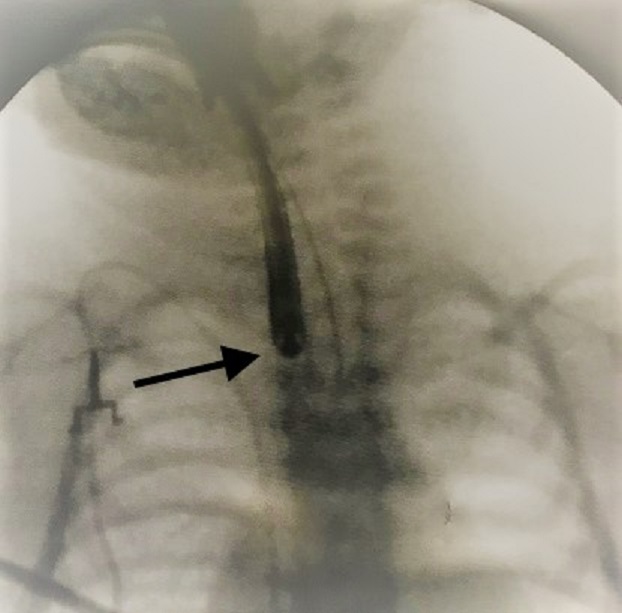

Figure 1

Case 1: The babygram shows the tip of the naso-esophageal tube at the level of the 7th thoracic vertebra. Hyperlucency around the tube mimics the upper esophageal pouch (arrow). The presence of air in the stomach/bowel loops is noted.